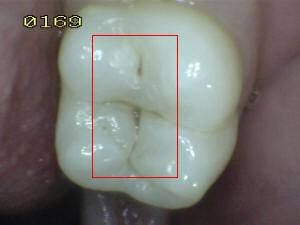

Sistema Internacional para la Detección y Evaluación de Caries (ICDAS)

¿Determine los códigos pertinentes a cada imagen?

Click en el hipervínculo: Para comparar el resultado de su diagnóstico